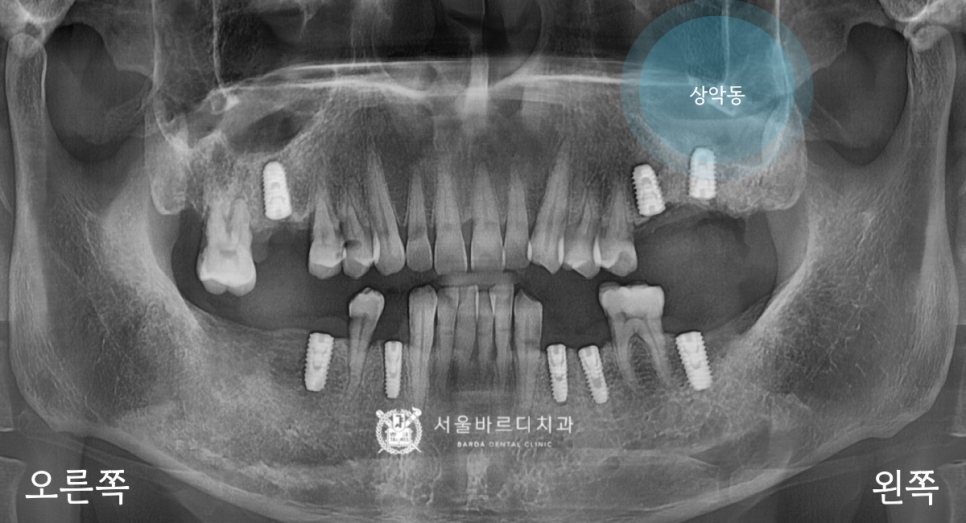

전반적인 뼈와 치아 상태를 확인하는

파노라마 엑스레이를 촬영하여 보니

기존에 이를 뽑은 자리가 많이 있었고,

오른쪽 위아래에 뿌리만 남은 부위가 있었습니다.

아래에 신경관이 있다면 위에는

상악동이라고 하는 공기주머니가 존재합니다.

얇은 막으로 둘러싸여 있어서

혹시라도 찢어지거나 뚫리게 된다면

축농증이 생길 수 있어서 조심하고 있습니다.